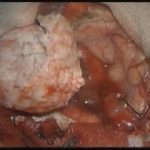

術中写真

摘出 後